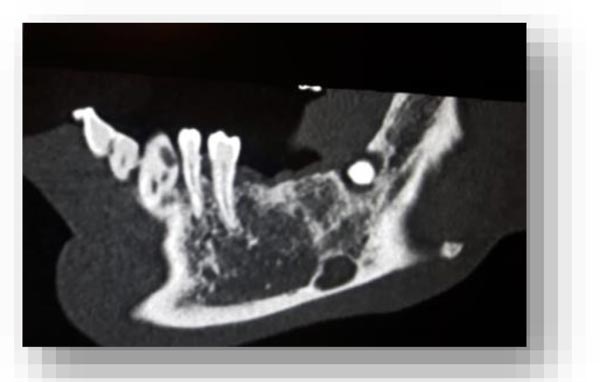

From the objective exam and the panoramic radiography, we observed the presence of multiple edentulous areas which needed to be rehabilitated. As part of an implant-prosthetic plan of care, Spiral Computerized Tomography was prescribed to him (Fig. 3), obtaining bi-dimensional reconstructions as panorex, parasagittal slices by multiplanar reformation and tridimensional reconstructions by volume rendering [12, 13].

In this radiographic exam, we found an oval notch with radiolucent, clear and regular borders, located in the inferior portion of the horizontal branch of the mandible, on the lingual side, near the angle of the mandible, and below the mandibular canal. The X-ray allowed precise measurement showing a height ranging between 13.5 mm and 17 mm and breadth between 6 and 8 mm (Figs. 4-5).

The bi-dimensional reconstructions in parasagittal slices also permitted better identification of the closeness of the bone cavity to the canal of the alveolar inferior omolateral nerve, whereas the computerized volume rendering offered a more accurate view of the surrounding anatomical features (Figs. 6-12).